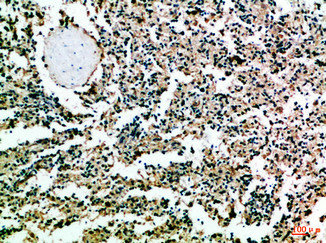

Immunohistochemical analysis of paraffin-embedded Human-tonsil, antibody was diluted at 1:100

CSB-PA338154

Immunohistochemical analysis of paraffin-embedded Human-spleen, antibody was diluted at 1:100